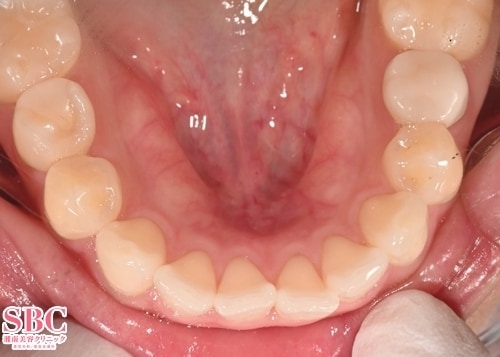

施術後7ヶ月後

しっかり内に下がって美しいアーチになりました